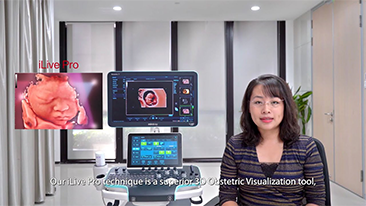

Geoptimaliseerde workflows in gynaecologie en verloskunde zijn noodzakelijk ter ondersteuning van grote pati?ntenvolumes aan screeningbezoeken voor vrouwen. Misvormingen van het centrale zenuwstelsel (CZS) zijn bijvoorbeeld een van de meest voorkomende aangeboren afwijkingen. Als gevolg van verschillende beeldvormingscondities, zoals een slechte foetale positie, is de MSP zeer moeilijk te vinden in een 2D-echografie. Daarom kunnen geautomatiseerde detectie en metingen de scaneffici?ntie sterk verbeteren.